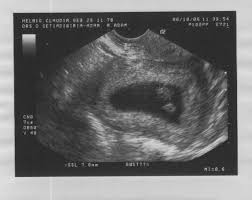

Aber das sieht sehr nach dem berühmten Dottersack aus. Ähnliche Fragen zum Thema Schwangerschaft und Geburt. Ultraschall-Video der Woche Du bist schon ganz neugierig auf das erste Ultraschall-Video deines Babys.

Alle series van Zwilling JA. Bei eineiigen Zwillingen ist im Ultraschall deutlich zu sehen dass sie sich eine Embryonalhülle teilen. Hcg wert 7 ssw zwillinge.

Der helle Kreis mit dunklem Fleck über dem Embryo ist. Hier gibt es aber keine strenge Vorgabe. Zwillinge in einer Fruchthöhle. Zwillinge können auf zwei Arten entstehen. Bei eineiigen Zwillingen ist im Ultraschall deutlich zu sehen dass sie sich eine Embryonalhülle teilen Eineiige Zwillinge werden in der Medizin auch monozygote Zwillinge genannt SSW auf und bedarf einer häufigen Untersuchung per Ultraschall 7 SSW - Zwillinge - bei 61 kein Herzschlag und jetzt ungutes Bauchgefühl. Die Zahl der Zwillingsschwangerschaften ist in den letzten Jahren gestiegen. Wenn Sie durch eine Behandlung gegen Unfruchtbarkeit wie zum Beispiel durch künstliche Befruchtung schwanger wurden dann wird der erste Ultraschall vermutlich schon in der vierten bis fünften Woche der Schwangerschaft gemacht. SSW Zwillinge fest gestellt. Hcg wert 7 ssw zwillinge.